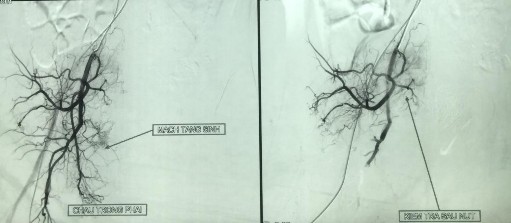

+ Trong nhóm nghiên cứu, có 1 ca u mạch ác tính (angiosarcoma) được chụp động mạch chọn lọc: bệnh nhân vào viện với triệu chứng thiếu máu cấp, XHTH thấp số lượng nhiều chảy máu ở vùng mông và hậu môn, hậu môn nhân tạo thông, không chảy máu. Kết quả chụp mạch thấy khối ở bụng tiểu khung phải được cấp máu từ nhánh của động mạch chậu trong phải, bệnh nhân đã được nút mạch chọn lọc 2 lần nhưng dấu hiệu lâm sàng vẫn không cải thiện. Bệnh nhân được chỉ định phẫu thuật để cầm máu và làm sạch, bệnh nhân đã được cắt cụt trực tràng đường bụng và tầng sinh môn, thắt động mạch chậu trong 2 bên, để hậu môn nhân tạo vĩnh viễn hố chậu trái.

Hình 4.2. Hình ảnh chụp mạch trước và sau can thiệp nút mạch

Chụp mạch thấy khối ở bụng tiểu khung phải được cấp máu từ nhánh của động mạch chậu trong phải, bệnh nhân đã được nút mạch chọn lọc nhánh của động mạch chậu trong 2 lần nhưng dấu hiệu lâm sàng vẫn không cải thiện. Khi phẫu thuật quyết định phải cắt cụt toàn bộ trực tràng và tổn thương qua đường bụng và tầng sinh môn, làm hậu môn nhân tạo vĩnh viễn hố chậu trái.

Đại thể đoạn hậu môn trực tràng dài 28cm mở qua niêm mạc nhẵn, thanh mạc mềm mại, các mảnh sinh thiết cắt vào thành trực tràng phía ngoài lớp cơ và tổ chức xơ mỡ có u hướng đến vi thể là Sarcoma mạch ở thành trực tràng.